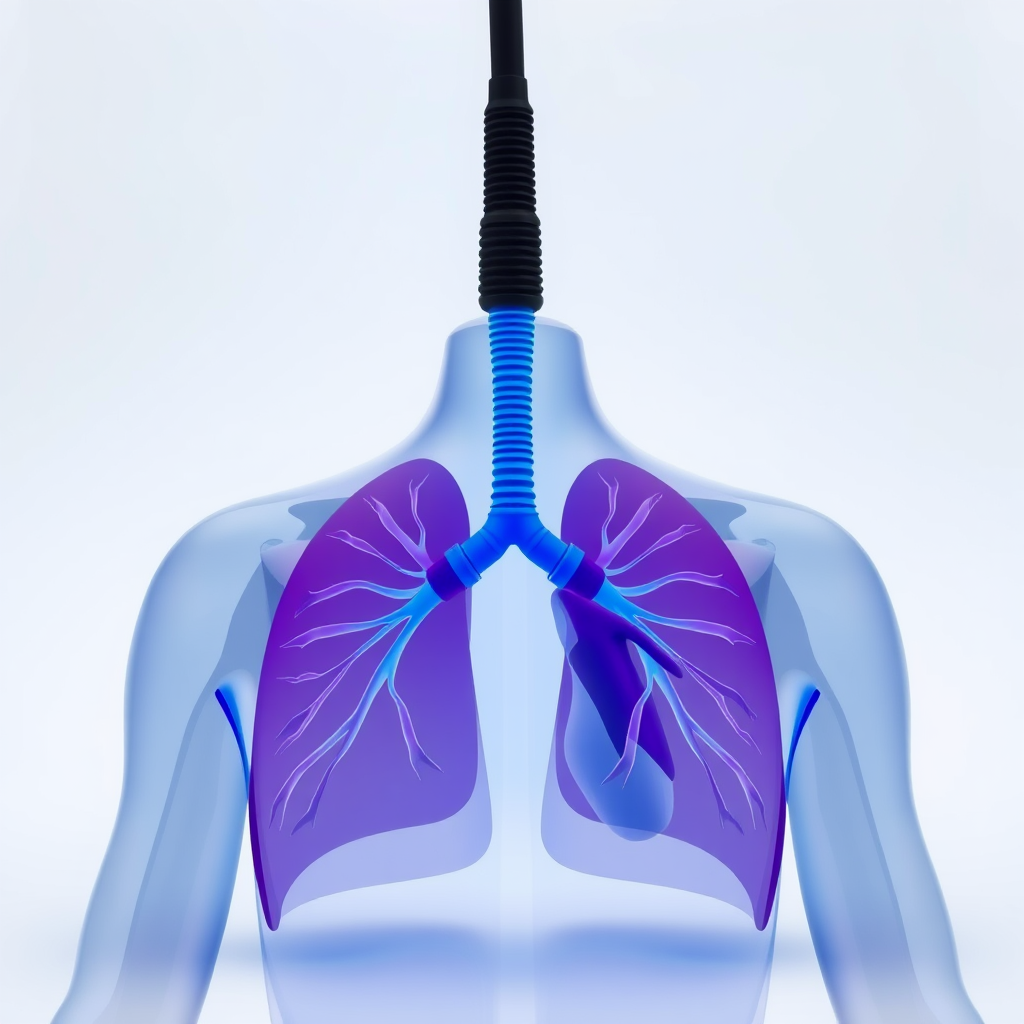

A clínica de fisioterapia cardiorrespiratória oferece uma gama de benefícios que impactam diretamente a saúde respiratória e cardiovascular dos pacientes.

Um dos principais benefícios da clínica de fisioterapia cardiorrespiratória é a melhora da capacidade respiratória.

Os exercícios respiratórios ajudam a expandir os pulmões e aumentar a eficiência respiratória.

Isso é especialmente importante para pacientes com doenças pulmonares crônicas.